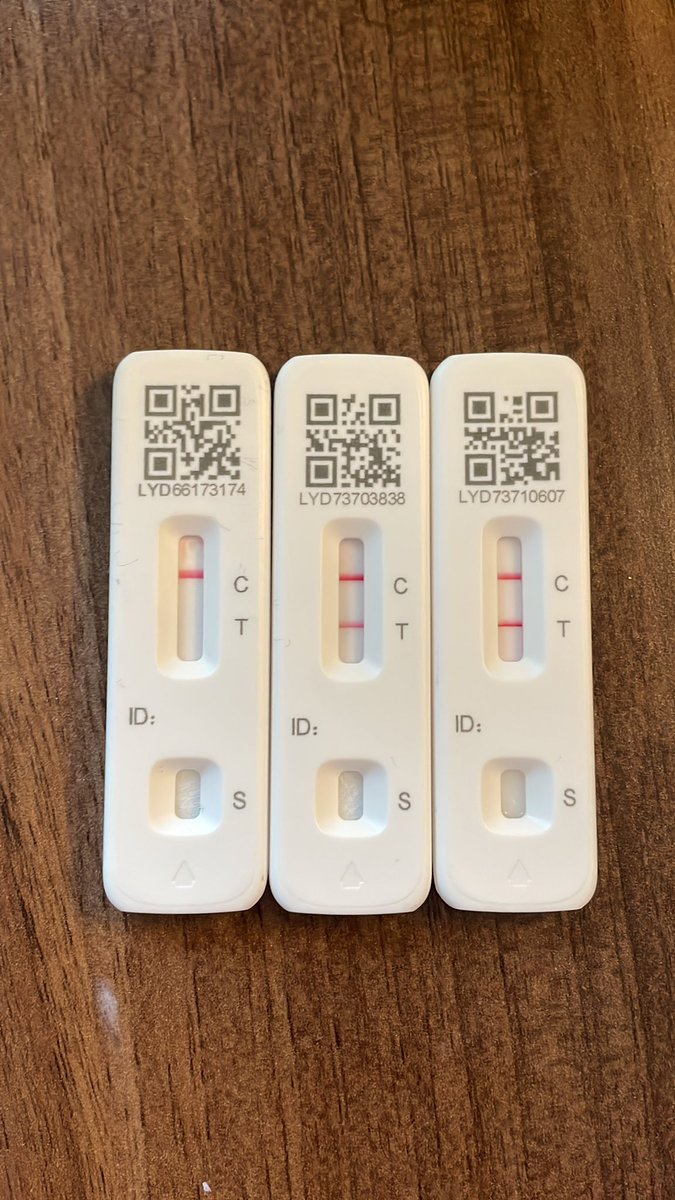

A pleasure to be on BBC News (UK) to whistleblow on poor #COVID19 testing process that plays with lives Full story BBC Panorama at 7.30pm tonight BBC1 @UoN_BDI @UoN_ECR_Soc University of Nottingham Students' Union Uni of Nottingham Press Office Uni of Nottingham #WeAreUoN BBC East Midlands BBC Nottingham Lilian Greenwood UoN Medicine and Health Sciences Nottingham Research